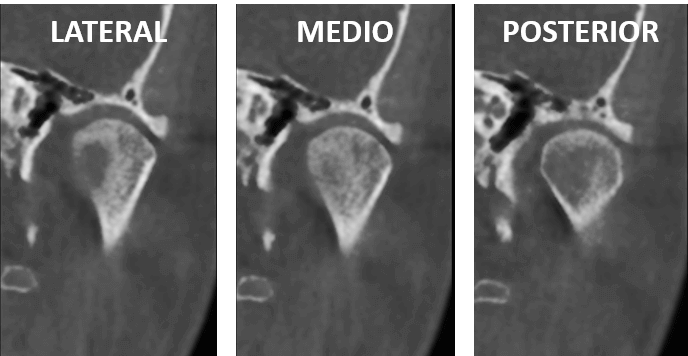

Fig.4

En cortes coronales de la ATM del lado izquierdo (Fig.4) se observa solo el aumento de la densidad ósea sin mayor evidencia de cambios morfológicos articulares en comparación con los cortes sagitales del mismo lado de la ATM. Así también en la representación tridimensional (Fig.5) se observan leves cambios morfológicos en el cóndilo mandibular izquierdo.